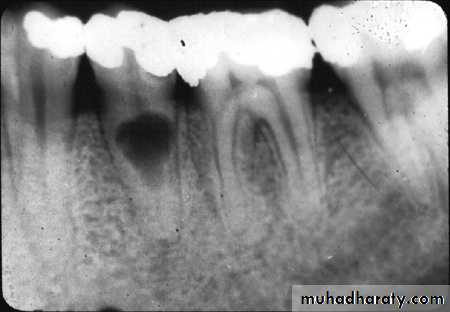

• Radiographic changes show:

– Chronic apical periodontitis in longstanding cases.

– In young patients, low grade longstanding irritation stimulates periapical bone deposition, i.e. condensing osteitis. Radiograph shows areas of dense bone around apices of involved teeth.

• Vitality Tests

– Tooth may respond feebly or not at all to thermal test, unless one uses extreme cold– More current than normal is required to elicit response by electric pulp tester.